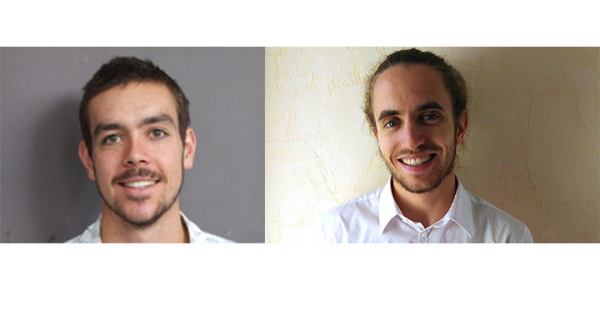

Aurélien (PH 2019) et Stenzel (IM 2019) tous deux diplômés d’une école de Grenoble INP et en première année de thèse au Grenoble Institut des Neurosciences, travaillent sur des thématiques liées à l’IRM.

L'imagerie par résonance magnétique (IRM) est une technique d'imagerie médicale permettant d'obtenir des vues en deux ou en trois dimensions de l'intérieur du corps de façon non invasive avec une résolution en contraste relativement élevée. Cette technique fait l’objet d’améliorations permanentes grâce aux travaux de nombreux chercheurs dont Stenzel Cackowski et Aurélien Delphin, respectivement diplômés de Grenoble INP – Ensimag et Grenoble INP – Phelma, qui effectuent tous les deux un doctorat au Grenoble Institut des Neurosciences (GIN).